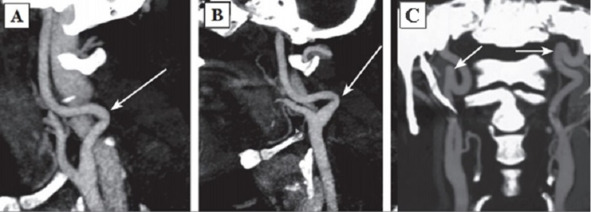

Fig. 2: Types of pathologic deformations according to SCT AG data: A – Type 1 septal stenosis (angle over 60°) (arrow indicated); B – Type 2 septal stenosis (angle from 30 to 60°) (arrow indicated); C – Type 3 septal stenosis (angle less than 30°) (arrow indicated).

The permanent effect of the force vector of arterial blood pressure on dysplastic vascular wall was discussed earlier as the most intensive initiating agent forming a pathologic tortuosity of the ICA [145]. In 1961 H. Metz offered his own classification of ICA deformations. The author supposed that the intensity of the process depended on dysplastic changes of the vascular wall and vessel configuration and divided septal stenoses of the ICA into three types:

Type 1: artery kink at an angle over 60°(Fig. 2A);

Type 2: artery kink at an angle from 30 to 60°(Fig. 2B);

Type 3: artery kink at an angle less than 30°(Fig. 2C) [182].